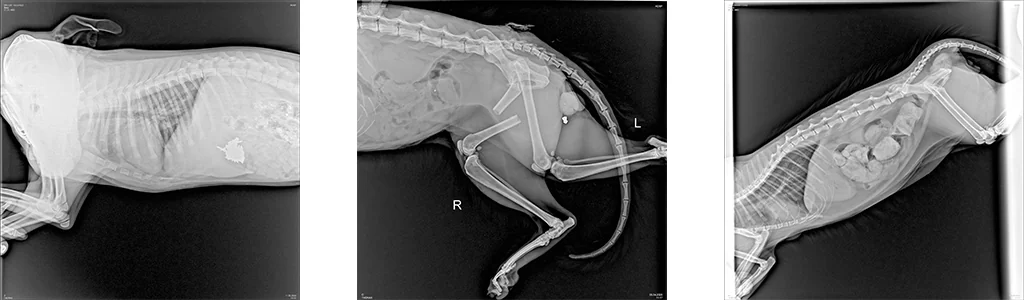

Одним из самых современных и информативных методов диагностики в ветеринарии является рентгенография. В клинике «Умная ветеринария» данный метод исследования проводится для постановки диагнозов при различных заболеваниях животных на цифровом рентген-аппарате высокого класса, позволяя ветеринарным врачам клиники получать ценную информацию о здоровье животных и назначать эффективные варианты лечения.

В ветеринарии рентгенография — это универсальный и незаменимый вид диагностики, один из самых точных, удобных, экономически выгодных для потребителя услуг неинвазивных методов диагностических исследований, используемый для визуализации внутренних структур животных.

Благодаря цифровой рентген-диагностике специалисты «Умной ветеринарии» получают быстрое изображений интересующей области исследования в виде снимка высокого качества на экране монитора, при этом современный цифровой рентген-аппарат, установленный в клинике, адаптирован под нужды ветеринарии, имеет специальное ветеринарное назначение и излучает минимально низкую дозу рентгеновского излучения для пациента, его владельцев, а также для специалиста рентген-кабинета.

Технология рентгенографии основана на использовании рентгеновских лучей, которые проникают через ткани животного. За небольшое количество времени излучение проходит сквозь мягкие ткани, такие как мышцы и внутренние органы, затем оно частично поглощается плотными структурами, такими как кости. Это позволяет получить высокоточное изображение скелета и органов тела животного.

Во время процесса рентгенографии рентгеновские лучи фиксируются на цифровой панели, создавая темный силуэт скелета животного на белом фоне. Мягкие ткани, внутренние органы, отображаются в виде различных оттенков серого в зависимости от их плотности.